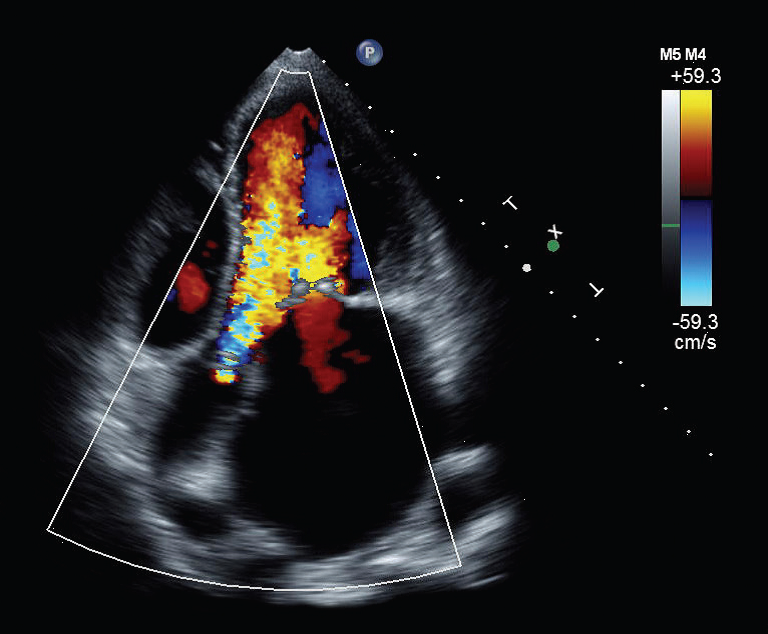

Echocardiography Tutorial Echocardiographic Modes